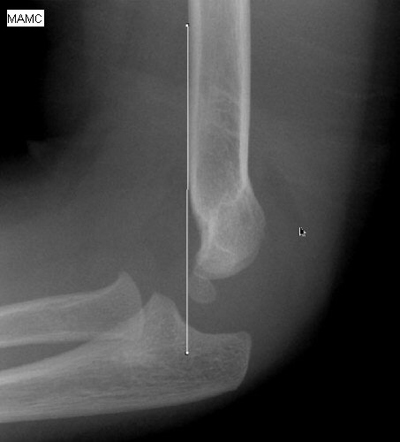

Step 4: Anterior Humeral line

This line should intersect the middle third of the capitellum on the lateral view. Fractures usually result in displacement of the capitellum posteriorly (versus anteriorly). If the film is not a true lateral, interpretation of the anterior humeral line becomes fallible.

This radiograph depicts a normal anterior humeral line: